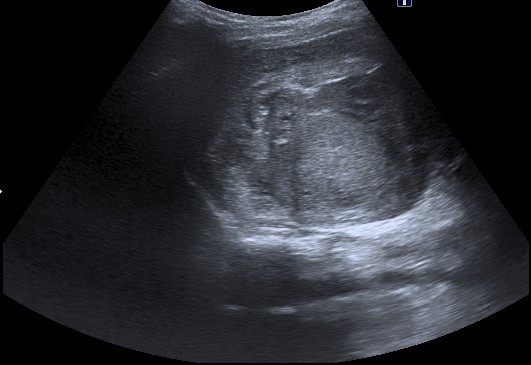

Ecografía:

- Masa renal bien definida e hiperecogénica de debido a la posible presencia de hemorragia, grasa, necrosis y raramente calcios.

- Las calcificaciones son raras. Su morfología es curvilínea (a diferencia del neuroblastoma = puntiforme).

- En ocasiones es posible diferenciar una pseudocapsula correspondiente a tejido renal sano comprimido.